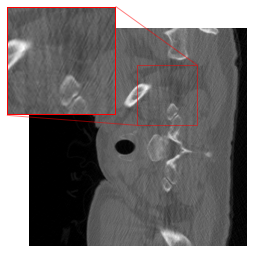

However, our application of this strategy in CT results in artifacts (cf. Figure 1(c)) at the patch boundaries, showcasing a sudden shift from intense to subtle smoothing with the cropping strategy. A reason for this might be that the errors are typically not Gaussian white noise, but more involved. For mitigating the artifacts, we modify the cropping approach of [47] by implementing padding in the output of the FBP to align with the network architecture. The DRUNet architecture operates solely on images sized as multiples of due to its four downsampling steps, whereas the LoDoPaB-CT dataset comprises images of size , which does not conform to this requirement. To address this, we apply mirror padding to enlarge the images to before passing them through the network and subsequently cropping them back to the original size of Figure 2 illustrates the suitability of the proposed strategy. (We point out that the image depicted in Figure 2 represents one of the most challenging reconstructions within the dataset.)

Effectiveness of the Rotational Augmentation

To evaluate the impact of rotational augmentation, we conducted an experiment by training two networks: one with rotational augmentation and the other without. The objective was to investigate the network’s response to input images under different orientations. Specifically, we applied two scenarios: firstly, inputting images as they are, and secondly, rotating them by 90° before feeding them into the networks. Results depicted in Fig. 3 illustrate a noteworthy observation. For the network with rotational augmentation during training (cf. 2(e) and 2(f)), the output remains consistent regardless of the input image’s orientation. However, for the network trained without rotational augmentation (cf. 2(c) and 2(d)), the output varies between the normal and rotated input scenarios. This experiment highlights the effectiveness of rotational augmentation in achieving network equivariance and ensuring consistent performance across different orientations of input images.